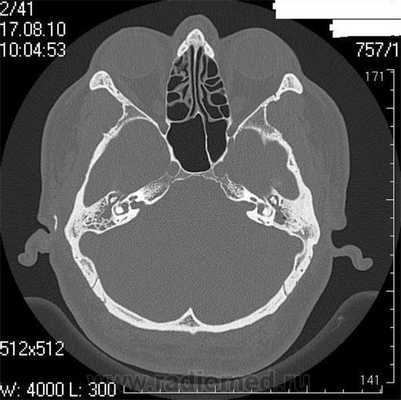

Кости черепа: поражение костей свода черепа начинается с формирования зоны изолированного остеолиза, диаметром несколько сантиметров, с четкими, фестончатыми контурами (osteolysis circumscripta). Зона остеолиза распространяется вширь, занимая значительные участки свода черепа, тогда как в ее центре формируются бесструктурные участки уплотненной кости. Хаотичное сочетание зон остеолиза и остеосклероза в промежуточной стадии болезни придает ландкартообразный рисунок рентгенологической картине. Свод черепа утолщается, приобретает бугристую поверхность, его размеры увеличиваются (рис.1а). В стадии стабилизации остеосклеротические изменения преобладают, создавая весьма характерный "ватный" рисунок. Свод утолщен до 1,5-2 см, редко больше. Турецкое седло, передняя черепно-мозговая ямка уплощены, тогда как задняя может провисать (рис.1б).

Рис. 1. КТ черепа (а) в аксиальной проекции демонстрирует утолщение костей свода черепа; на рентгенографии в боковой проекции (б) отмечается уплощение рельефа передней черепной ямки, провисание задней черепной ямки